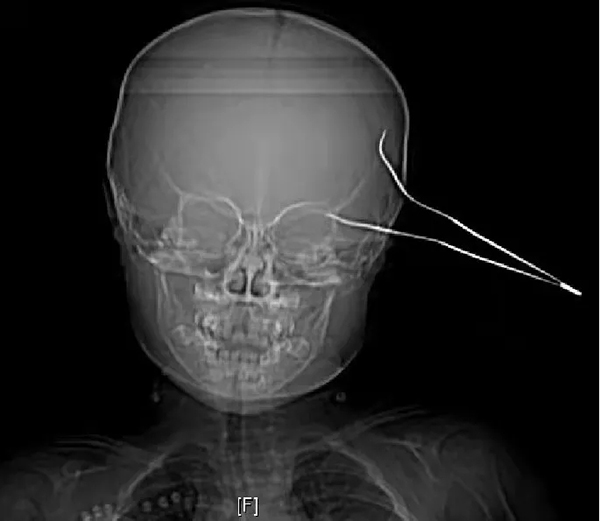

徐醫(yī)附院:15cm鑷子直插兩歲女童大腦,神經(jīng)外科成功救治,患兒轉(zhuǎn)危為安

患兒笑笑(化名)是一位天真活潑,率真可愛的女孩,在父母的呵護(hù)下快樂(lè)成長(zhǎng)。然而,天有不測(cè)風(fēng)云, 10月23日中午10時(shí)許,笑笑在玩鬧過(guò)程中不慎摔傷,致15cm長(zhǎng)的金屬鑷子刺入頭部,當(dāng)時(shí)傷口少量出血,笑笑因疼痛哭鬧不止,家人將笑笑緊急送至當(dāng)?shù)蒯t(yī)院,頭顱CT示左側(cè)顳部條狀致密影穿透左側(cè)顳骨,深入左側(cè)顳葉,情況十分危急,當(dāng)?shù)蒯t(yī)院建議轉(zhuǎn)至徐醫(yī)附院進(jìn)行手術(shù)治療。

徐醫(yī)附院急診醫(yī)護(hù)人員接診后,立即聯(lián)系神經(jīng)外科值班醫(yī)生進(jìn)行會(huì)診。神經(jīng)外科醫(yī)師張桐會(huì)診發(fā)現(xiàn),笑笑左側(cè)顳部金屬質(zhì)鑷子兩支齒的尖端均深入皮下,余在外的鑷子底部已經(jīng)嚴(yán)重彎曲變形,由此可見患兒受傷時(shí)所受外力之大。張桐醫(yī)師查閱CT后立即向凌南主治醫(yī)師及劉勇主任醫(yī)師緊急匯報(bào)。劉勇主任團(tuán)隊(duì)經(jīng)過(guò)綜合討論和全面評(píng)估,認(rèn)為需要立刻進(jìn)行手術(shù),取出腦部異物,以免引發(fā)二次傷害和顱內(nèi)感染,于是,快速啟動(dòng)醫(yī)院綠色救治通道、與患兒家長(zhǎng)溝通、聯(lián)系手術(shù)室進(jìn)行術(shù)前準(zhǔn)備、聯(lián)合多學(xué)科進(jìn)行保障……一場(chǎng)與死神的賽跑正式開啟。

回憶起那天的情景,劉勇主任依舊歷歷在目,因?yàn)榇唐骑D骨的鑷子一端已刺破硬腦膜,刺穿大腦顳葉皮層,鑷子尖部直逼側(cè)裂大血管,萬(wàn)幸的是,鑷子尖并沒有刺破大腦中動(dòng)脈和重要靜脈。參與手術(shù)的王雷副主任醫(yī)師說(shuō):“劉主任經(jīng)常教導(dǎo)我們年輕醫(yī)生說(shuō),外科醫(yī)生遇事心要靜,手要穩(wěn),腦外科醫(yī)生尤其如此,心和手都要穩(wěn)如泰山。的確這個(gè)小女孩受傷的地方太危險(xiǎn),太考驗(yàn)醫(yī)生的心理素質(zhì)和專業(yè)技術(shù)水平了。”劉勇主任補(bǔ)充說(shuō):“看著小女孩稚嫩可愛的小臉蛋,想著她以后如花般燦爛的人生,我們所有手術(shù)臺(tái)上的醫(yī)務(wù)人員就一個(gè)想法,就是盡自己最大的努力,確保手術(shù)成功!”